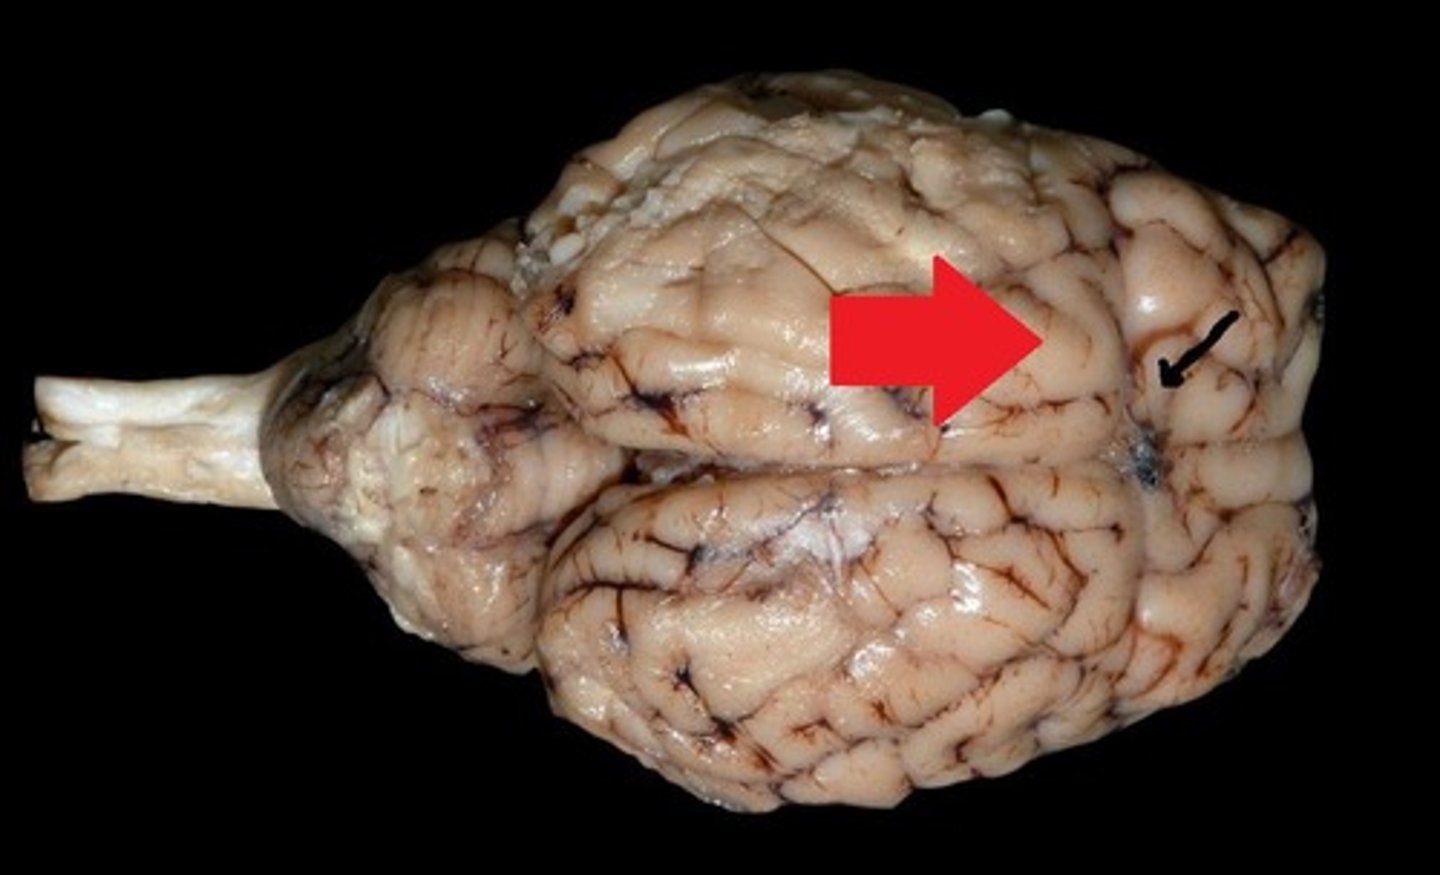

Frontal lobe

Controls cognitive processes such as planning and the inhibition of drives (#4)

Parietal lobe

Integrates sensory information and functions in spatial perception (#5)

Temporal lobe

Functions in auditory perception and long-term memory (#6)

Occipital lobe

Receives sensory information from the eyes (#7)

Sulci

Furrows in the folds of the cerebrum (#19)

Gyri

Bulges in the folds of the cerebrum (#20)